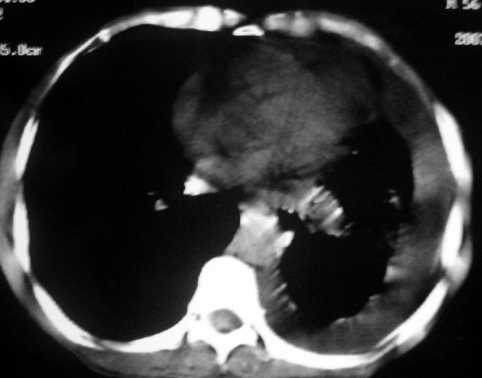

男,54岁,咳嗽,气喘半年,胸痛一月.

血性胸水

1.左肺下叶中心性肺癌伴阻塞性肺炎,肺不张.

2.左侧胸腔积液,心包积液

左侧中心型肺癌并阻塞性肺炎、肺膨胀不全,左胸腔、心包积液